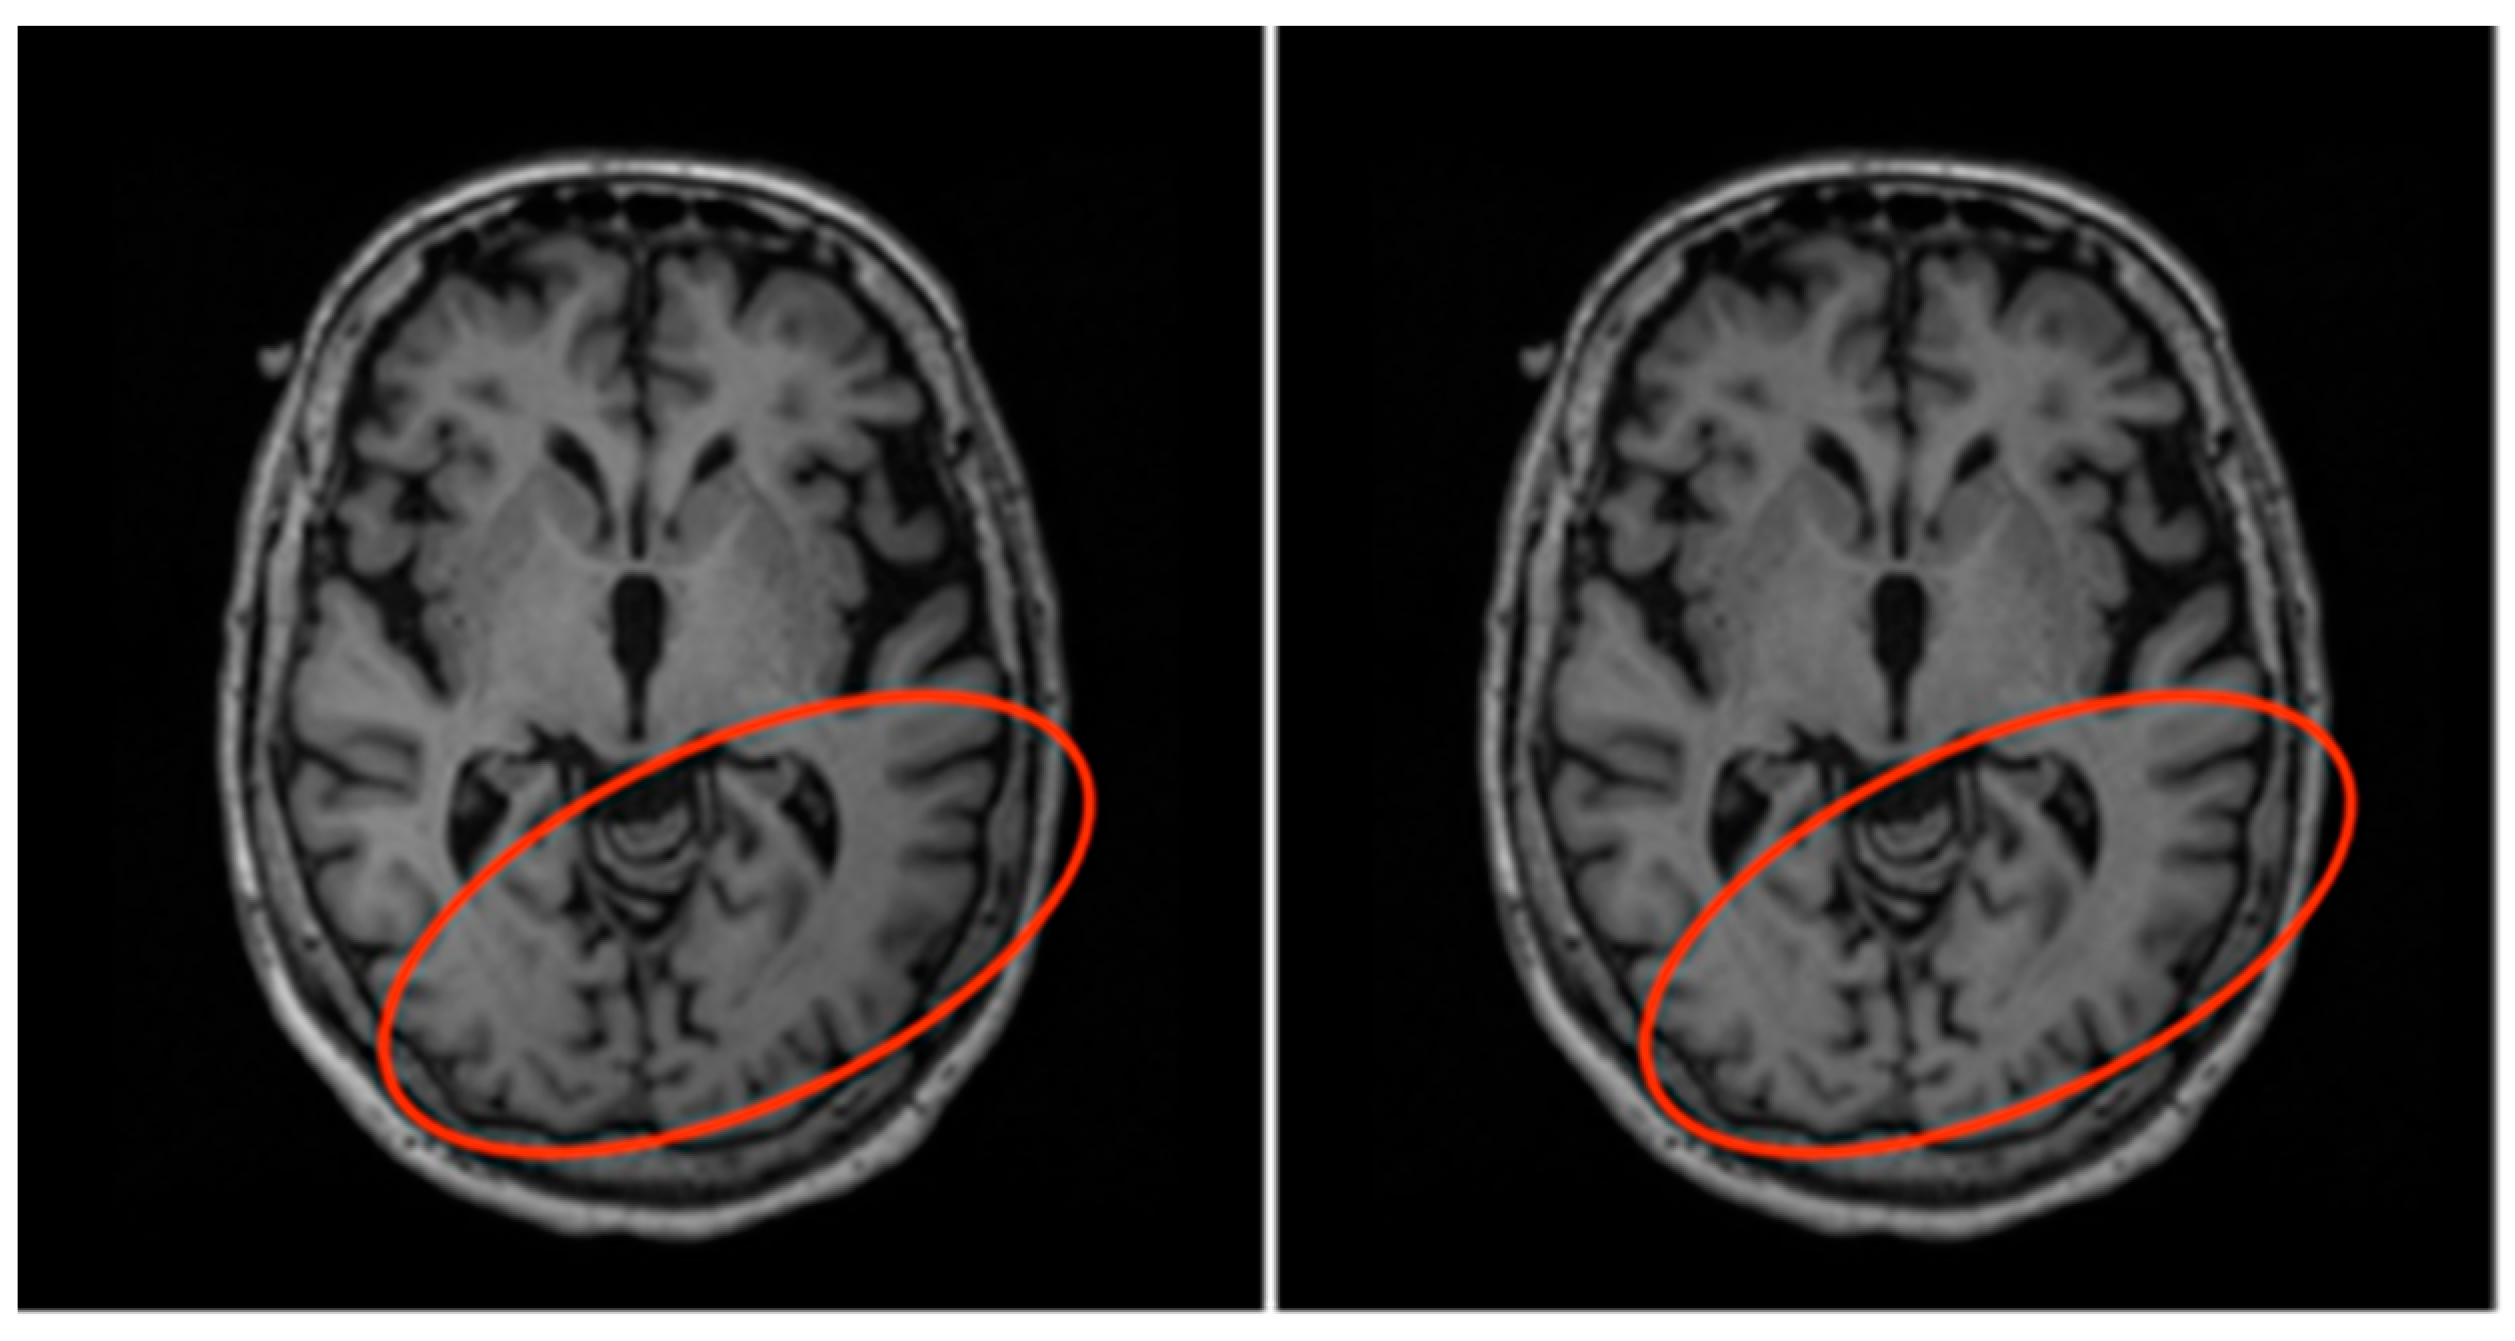

3.1. Data Description

- Have high-quality hippocampus segmentation masks (preferably from manual segmentation), which have been proven to closely follow the morphometric characteristics of the actual hippocampi;

- Have hippocampus segmentation masks that are obtained using a clinically validated and standardized set of rules in order to ensure their inter-rater reliability;

- Contain sufficient data for both training and evaluation of our models.